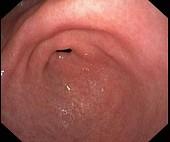

问题 女,28岁,间歇性上腹痛腹胀4年,无呕吐。抗酸制剂治疗无效,查体上腹轻压痛,B超肝查未见异常,胃镜检查如图。最有可能性的诊断是 ( )

选项 A.消化性溃疡 B.胃癌 C.胆囊炎 D.胃下垂 E.萎缩性胃炎

答案 D